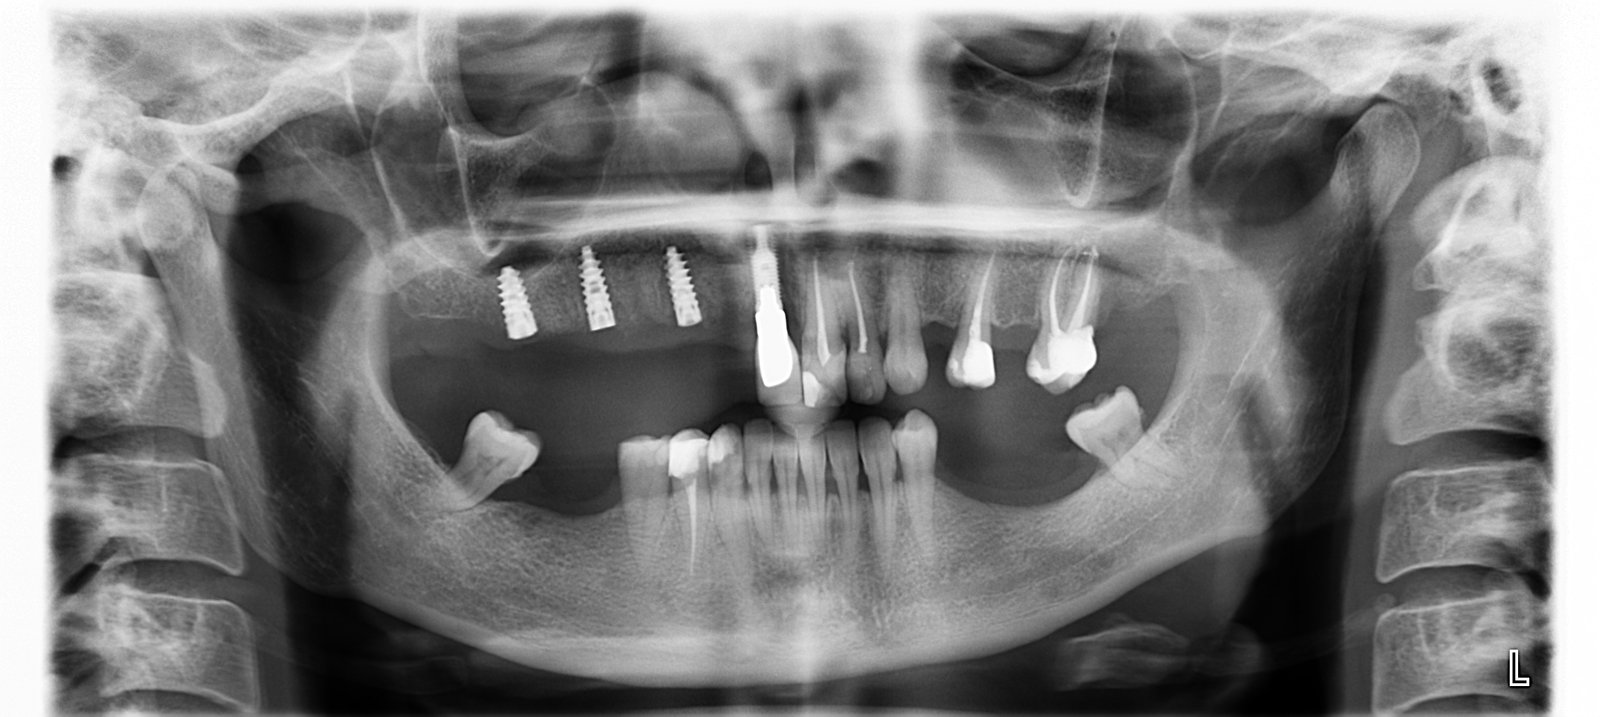

el implante del 11 no se cual es

necesitamos la marca y referencia del implante de la pza 11

Implante en el central, es conexion interna

Hola, me gustaria saber que implante lleva este paciente en el central, tengo que rehabilitarlo, muchas grcaias de antemano.

Implantes en 12 y 22

Buenas tardes compañeros, Agradecería ayuda identificando el tipo de implante y coenexion utilizada en estos implantes. Lo único que puedo aportar es que son cementados y al tratar de remover [...]

Implantes Crevillent

buenas noches. Estos implantes fueron colocados en una clínica de crevillente hace aproximadamente 10 años. El dentista cerró la clínica y se marchó.